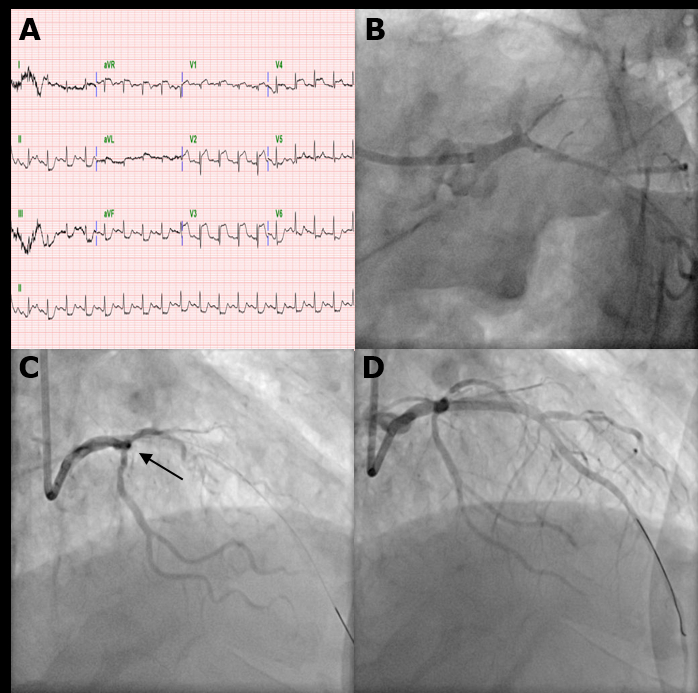

An 84-year-old male was transferred from another hospital for decreased mentality with right hemiparesis. He had visited the hospital for chest pain. While waiting for examination, he suddenly collapsed with desaturation and was transferred for proper management. Computed tomography angiography showed left proximal ICA occlusion and the left anterior cerebral artery with the left middle cerebral artery supplied via the anterior communicating artery. Electrocardiography indicated anterior wall ST elevation myocardial infarction (STEMI). Portable echocardiography findings suggested left anterior descending (LAD) artery territory insult. After a discussion with the attending cardiologist, we decided on intervention for STEMI first. After loading dual antiplatelet agents, PCI was done. After the procedure, we did EVT on the left ICA. The first pass effect was achieved by aspiration thrombectomy.